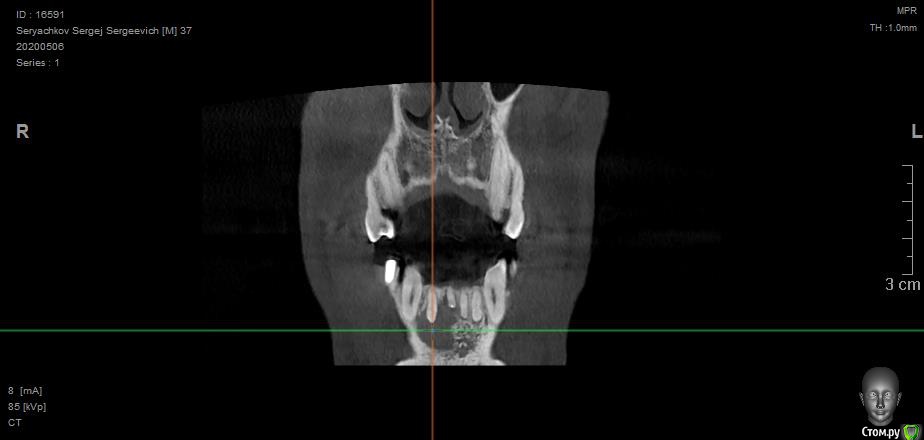

olstrill Опубликовано 24 мая, 2020 Поделиться Опубликовано 24 мая, 2020 Добрый день. Под передними резцами обнаружилась обширная киста. В трёх клиниках предложили различное решение:1. Удаление 2-х поражённых зубов, разбираемся с кистой, ждём полгода, потом вкручиваем Dentium Implantium. На период ожидания верхняя часть вырванных зубов крепится на пластинку, которая как-то крепится на соседние зубы, нагрузка на заглушки до установки имплантов запрещена.2. Удаление 6-ти передних зубов (включая клыки), установка на их место 3-х Dentium Implantium + коронка на 6 удалённых зубов. Врач говорит - как удалим зубы сразу поставим временную коронку, мол эстетически будет самое лучшее решение, а также это самый быстрый вариант, мол пару месяцев - и готово.3. Удаление 2-х поражённых зубов, обточка соседних и установка на шесть передних длинной коронки. Средний вариант по срокам и стоимости. Склоняюсь к первому варианту, но волнуют следующие вопросы:1. Под повреждёнными зубами, как я понимаю, нету или мало кости, в которой можно было бы закрепить импланты. Что там нарастёт за полгода ожидания непонятно. Врач говорит, что нужно будет ещё дополнительно наращивать кость, но не будет ли это половинчатым решением? Подозреваю, что импланты будут подвижны, что, как я понимаю, не хорошо.2. Импланты в зоне улыбки могут эстетически выглядеть не очень, к тому же могут просвечивать через десну.3. Будут слабо выражены переходы между имплантами, десна там может принять прямую форму, что эстетически будет смотреться так себе.3. Временные зубы на месте вырванных на период восстановления кости, врач говорит - периодически будешь приходить и будем править тебе пластинку с "заглушками". Думаю потеряю я эту пластинку в первую неделю и буду ходить полгода с дырой впереди (что, в связи с работой, неприемлемо). Хотелось бы услышать мнение экспертов - правильные ли предложены методы решения проблемы и обоснованны ли переживания. Ссылка на комментарий

St. Опубликовано 28 мая, 2020 Поделиться Опубликовано 28 мая, 2020 Добрый день. Ваше беспокойство вполне обосновано. Поэтому нужно пробовать сохранить эти зубы. То есть сначала перелечить каналы, дальше наблюдать за заживлением 6 и 12 мес, и уже после этого в случае необходимости обсуждать вопросы хирургии. Ссылка на комментарий